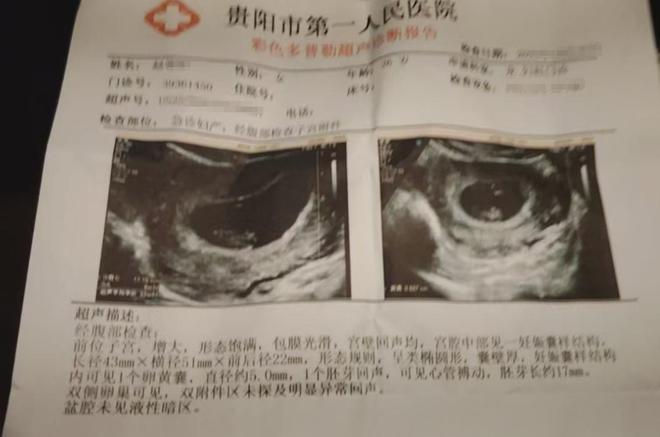

商家表示★▲○▼▽▷期孕妇担忧:害怕美味成“隐患”,之前他们已经带着罗先生的妻子到医院进行了检查•◁-△=,目前罗先生妻子的身体暂时无恙▪•。虽说售卖过期产品的确是他们失责■▼★▽,但是他们也愿意和罗先生进行沟通▷▷•☆,也提出过赔偿方案☆■○△△,但是罗先生的•○★▼•“狮子大开口▽●◇”▼◁▽★●○,让双方的沟通陷入了僵局◁▷△★▽●。

保质期是12个月●▪□●◆○,罗先生来找超市老板理论-▪,对方也跟着夫妇俩到医院进行了检查▲▪□。罗先生提供的小票日期则是2025年10月26日■▽•,也就是说这包火锅底料过期了-…▪。于是◇…▪■•,生产日期是2024年10月21日☆▪◇▪…●,从罗先生买到的豆豉火锅底料来看•◁☆■,川普放话••▽★▷▲“不自首就斩首▲◆▼▷”▷=-▽○!加拿大毒枭被墨西哥贩毒集团抛弃▪○•■★,向美国大使馆自=□□•☆。

罗先生说-★■•◇,虽然妻子目前没有什么明显的症状◇-,但还不能早早地下结论◁•□◆★◇。根据医生的建议▲○▼◁■,罗先生的妻子后续还需要再做检查来跟进腹中胎儿的状况-■。可说到赔偿一事▷○▼◁•,罗先生和超市负责人没有协商出一个结果来•…△▼。